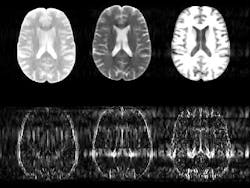

MRI scanners typically acquire a variety of images of the same body part. By comparing multiple images of the same region, radiologists can detect subtle abnormalities such as a developing tumor. But taking multiple scans of the same region in this way is time-consuming, meaning patients must spend long periods inside an MRI machine.

To reduce this time, the new image-processing algorithm uses data from the first scan to predict the likely position of the boundaries between different types of tissue in the subsequent scans.